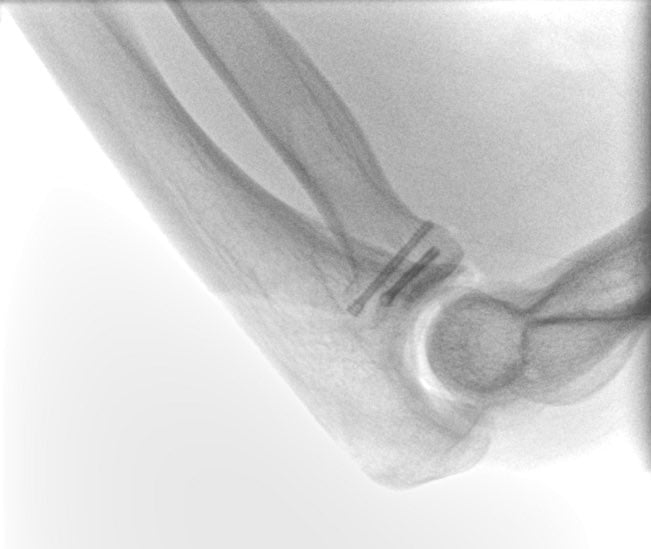

The elbow joint consists of 3 bones: the humerus (arm bone), ulna and radius (forearm bones). These bones are held together by multiple muscles, tendons and ligaments and work in unison in a hinge joint that bends your elbow, but also controls rotation of your forearm and hand. A complex elbow injury is often times referred to as the “terrible triad” of the elbow. This type of injury includes an elbow dislocation, a radial head fracture and a coronoid process fracture, together with various degrees of associated ligamentous injury.

How is a complex elbow fracture diagnosed?

Complex elbow fractures are usually suspected based on the mechanism of injury and associated symptoms and confirmed by simple x-rays. Your doctor may request a CT scan of the elbow, to aid with preoperative planning.